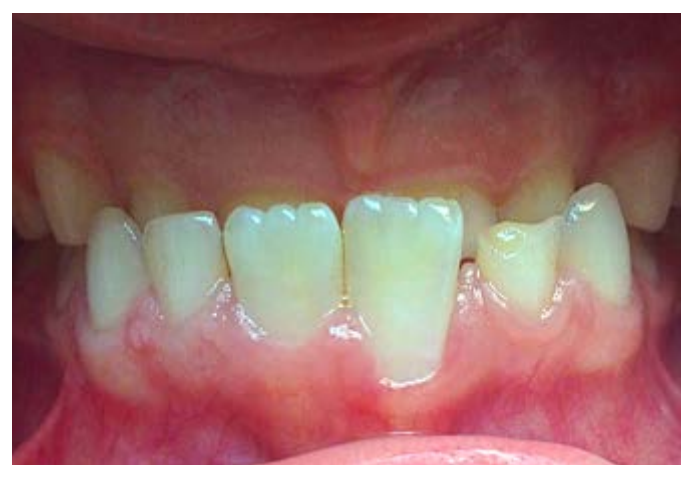

Первые признаки РД проявляются при сменном прикусе на этапе прорезывания постоянных резцов, чаще на нижней челюсти (рис. 1).

Рис. 1. До ортодонтического лечения: рецессия в области зуба 3.1